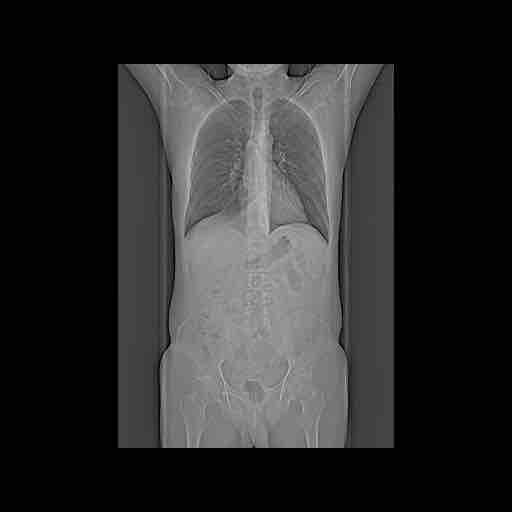

Om het makkelijker te maken hebben we de foto’s nog. Ook 2 gifjes, maar die zijn te groot, deze heb ik omgezet naar video’s, zodat we ik ze toch kan delen.

Nou hebben ze op een foto laten zien waar de tumor zit, daar stond ook een meet-lijn waardoor je de grootte kan zien. Hij is dus 2,2 cm en 6 weken geleden nog 3,4, het gaat dus goed. Verder houden we ons gewoon aan wat ze allemaal zeggen en gaan we gewoon mee in het advies.

Hierbij de foto’s:

Eersts voor de nerds:

Dan foto’s die voor hen blijkbaar belangrijk zijn.

Nog een overzicht.